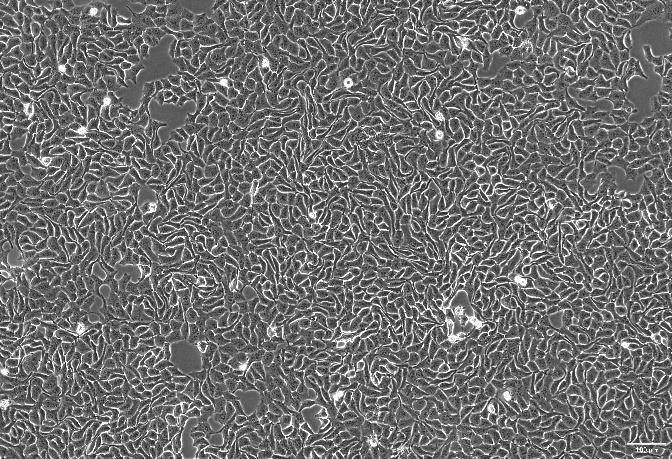

OriCell®T84 人结肠腺癌肺转移细胞系

T84细胞系常用于人结直肠癌的研究。

贴壁生长;上皮细胞样 |